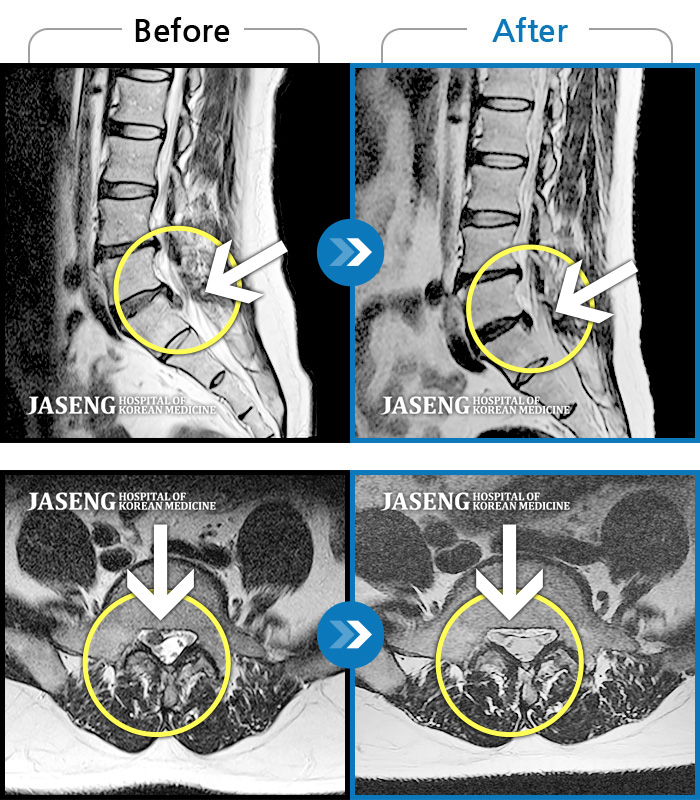

허리디스크

일산 · 배영현 원장

처음 내원 시 허리와 좌측 골반이 많이 아프고, 좌측 다리로 저림과 감각 저하가 있어서 보행이 원활하지 못했으며, 야간통으로 잠도 못 자고 통증 심하여 정상적인 활동이 힘든 상태셨습니다.

촬영시기

2023.09.16 ~ 2024.09.24

2024.10.04